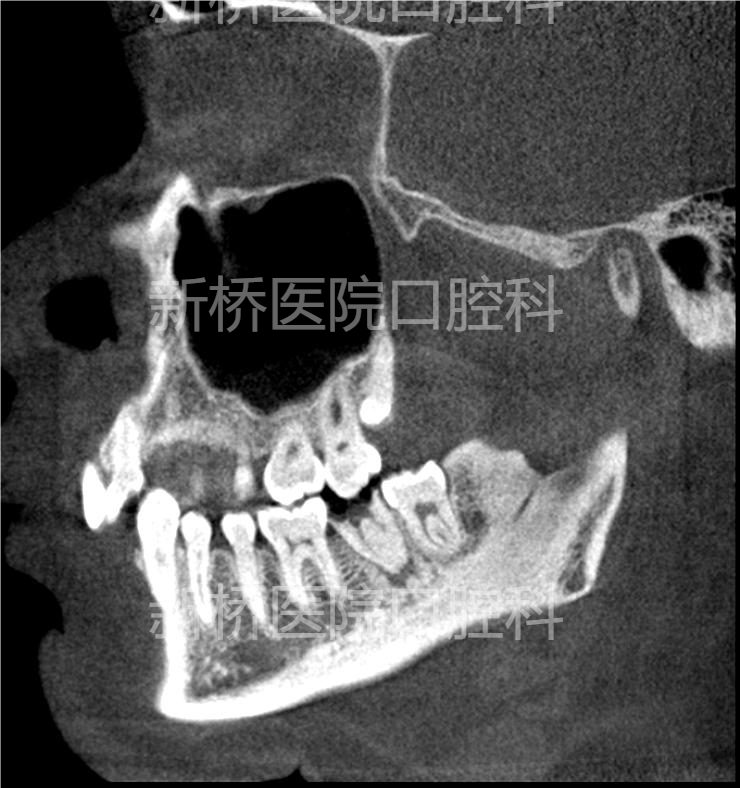

自体牙移植(auto transplantation , ATT) : 自体牙移植是将牙从一个位置移植到同一个体的另一位置,包括将埋伏、阻生、或萌出牙转移到其他缺牙部位牙槽窝内或手术制备的牙槽窝内。

本例采用3D数字化打印技术,术前模拟牙槽窝修整部位,术中用3D打印等比树脂牙试植,做到精准高效制备植入窝,减少供牙离体时间,减少供牙反复植入次数,极大减少供牙牙周膜损伤。